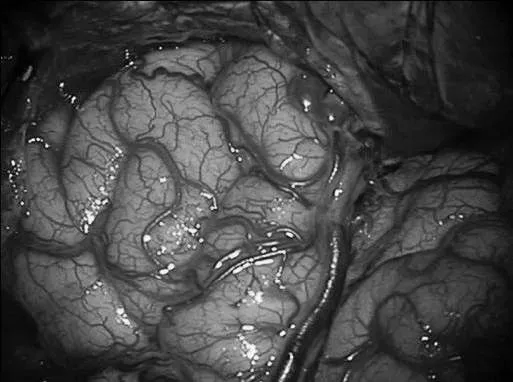

▼左侧翼点开颅,再次手术,显露前颞叶